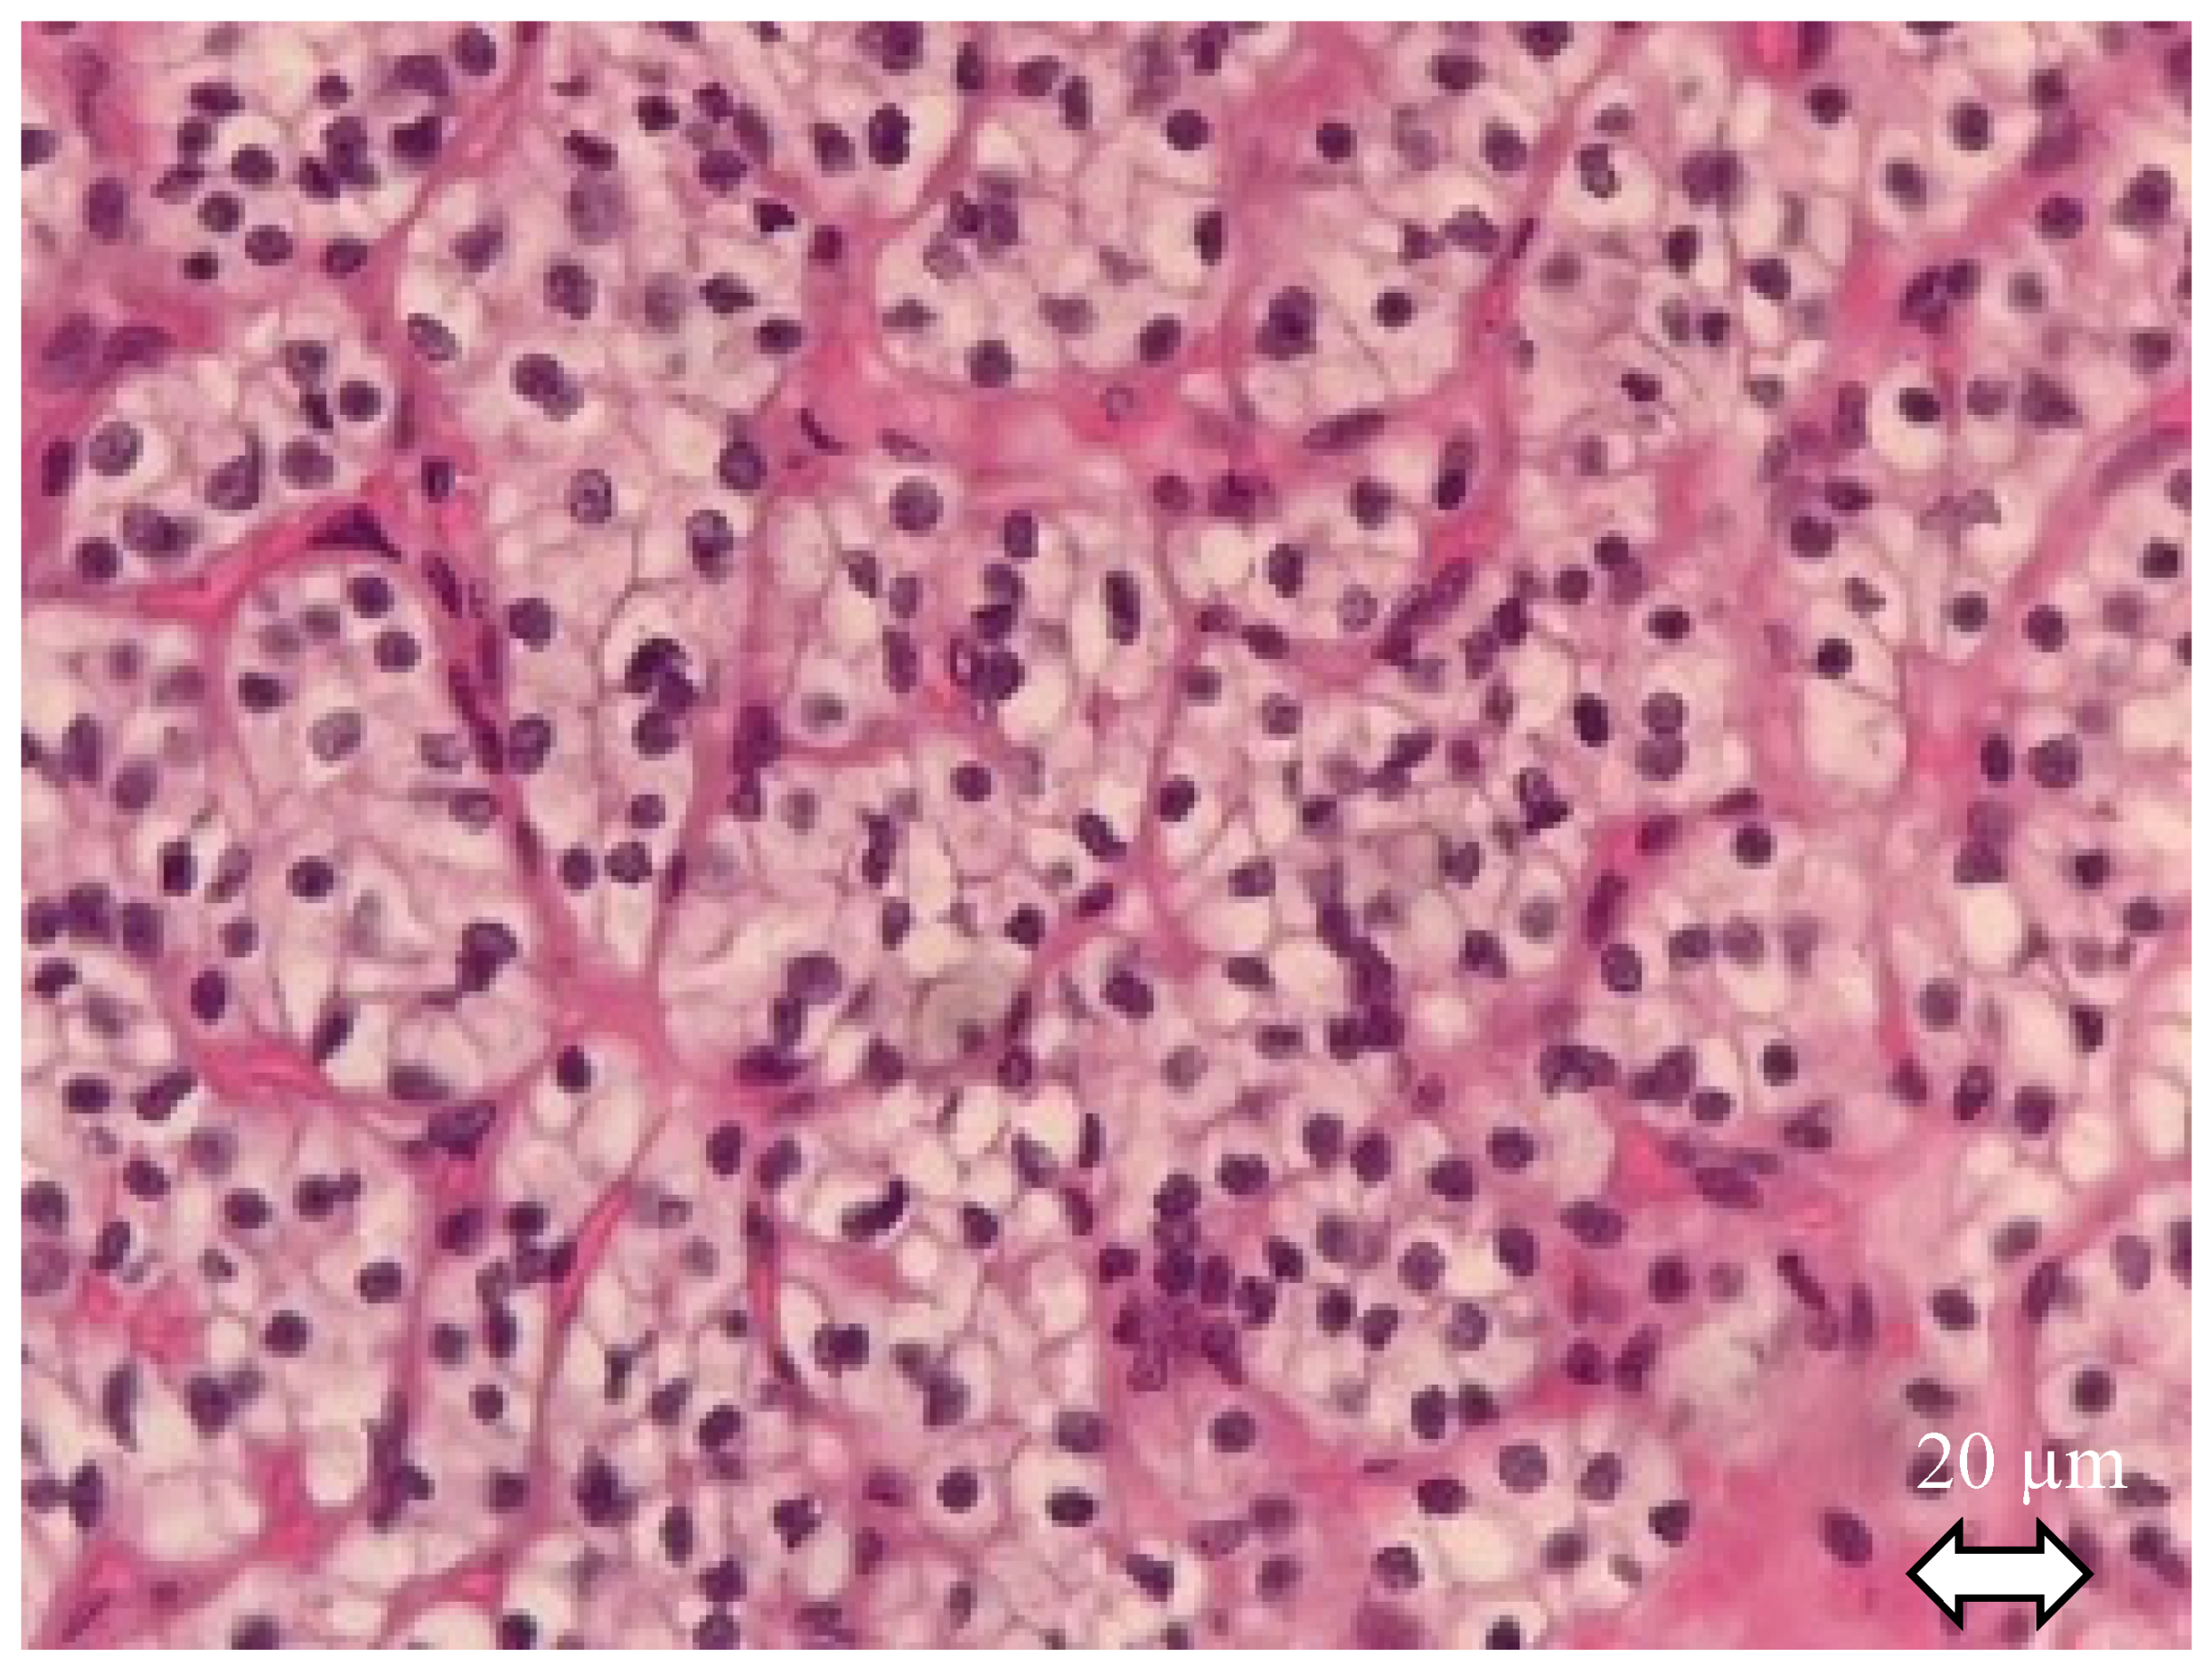

Making a precise diagnosis of the subtype is crucial given the wide alterity of related prognosis. After gross description, diagnosis of RCC, with histological features of the tissue sample, is always the first step before subtype identifying [12]: RCC tumor cells have abundant cytoplasm that is vacuolated, fluffy or granular, usually with indistinct cell borders (chromophobe renal cell carcinoma has distinct borders). Tumor nuclei have variable atypia, irregular contours, haphazard orientation with abnormal chromatin and variably prominent nucleoli (Figure 1).

Figure 1.

Clear cell renal cell carcinoma. Hematoxylin and eosin staining. The tumor shows solid alveolar growth pattern with regular network of small thin-walled blood vessels. Neoplastic cells have clear cytoplasm filled with lipids and surrounded by distinct cell membranes.